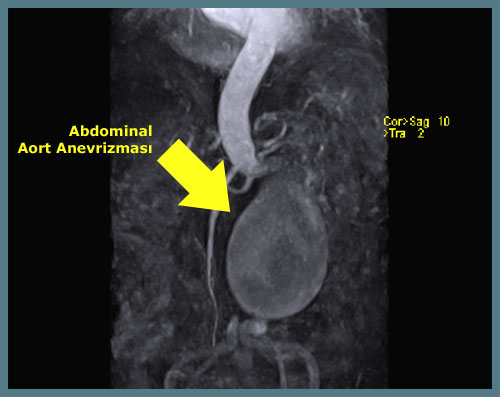

Anevrizma erkenden teşhis edildiğinde kalıcı tedavisi mümkündür. Ancak genelde anevrizmalar pek fazla şikayete neden olmadığı için çoğu kez yapılan incelemelerde tesadüfen saptanır. Anevrizmaların önemli bir kısmı doktor muayenesi ile belirlenebilir. Ancak anevrizma tanısında en basit yöntem ultrasonografidir. Ultrasonografi anevrizmaların tanısında basit, hızlı, ucuz ve güvenilir bir yöntemdir. Ultrasonografi ayrıca toplumda anevrizmalar için çok iyi bir tarama aracıdır. Altmış beş yaşın üzerindeki bütün erkeklerin hayatlarında en az bir kez ultrasonografi ile anevrizma yönünden değerlendirilmeleri gereklidir.

Anevrizma tanısında özellikle tedaviyi planlamak için başka yöntemlerde kullanılmaktadır. Bunlar bilgisayarlı tomografi, manyetik rezonans görüntüleme ve anjiografidir.

Bu yöntemler ile anevrizmanın ne kadar büyük olduğu (tedavi planlamasının en önemli öğesidir), nerede olduğu ve hangi organlarla ilişkide olduğu belirlenir. Anjiografi cerrahi girişimi plnalamak için genelde gerekmez, ama endovasküler anevrizma onarımı planlanırken çektirilmesi uygundur.